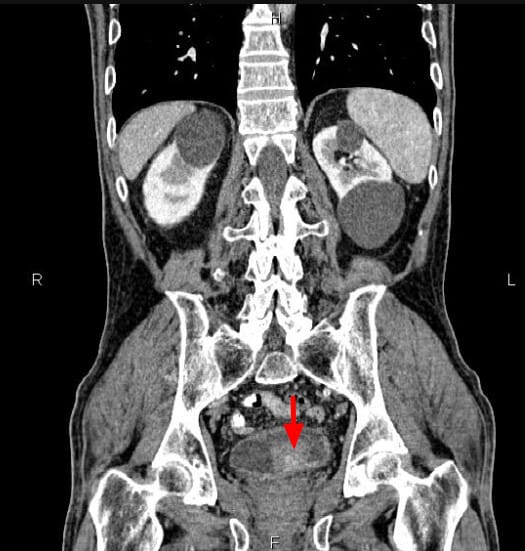

방광암 (Bladder Cancer)

[임상양상]

– 가장 특징적인 증상은 무통성 육안적 혈뇨입니다.

– 빈뇨, 배뇨통, 잔뇨감 같은 자극 증상이 동반될 수 있습니다.

– 진행 시 골반통, 수신증(요관 폐쇄), 체중 감소 등 전신 증상이 나타날 수 있습니다.

[진단]

– 소변검사: 혈뇨 확인.

– 소변세포검사: 암세포 확인 가능.

– 방광경검사(Cystoscopy): 진단의 gold standard, 직접 종양 확인 및 조직생검 가능.

– 영상검사(CT urography, MRI): 종양의 범위 및 전이 평가.

– 병리검사: 요로상피암(urothelial carcinoma), 편평상피암, 선암 등 조직학적 아형 구분.